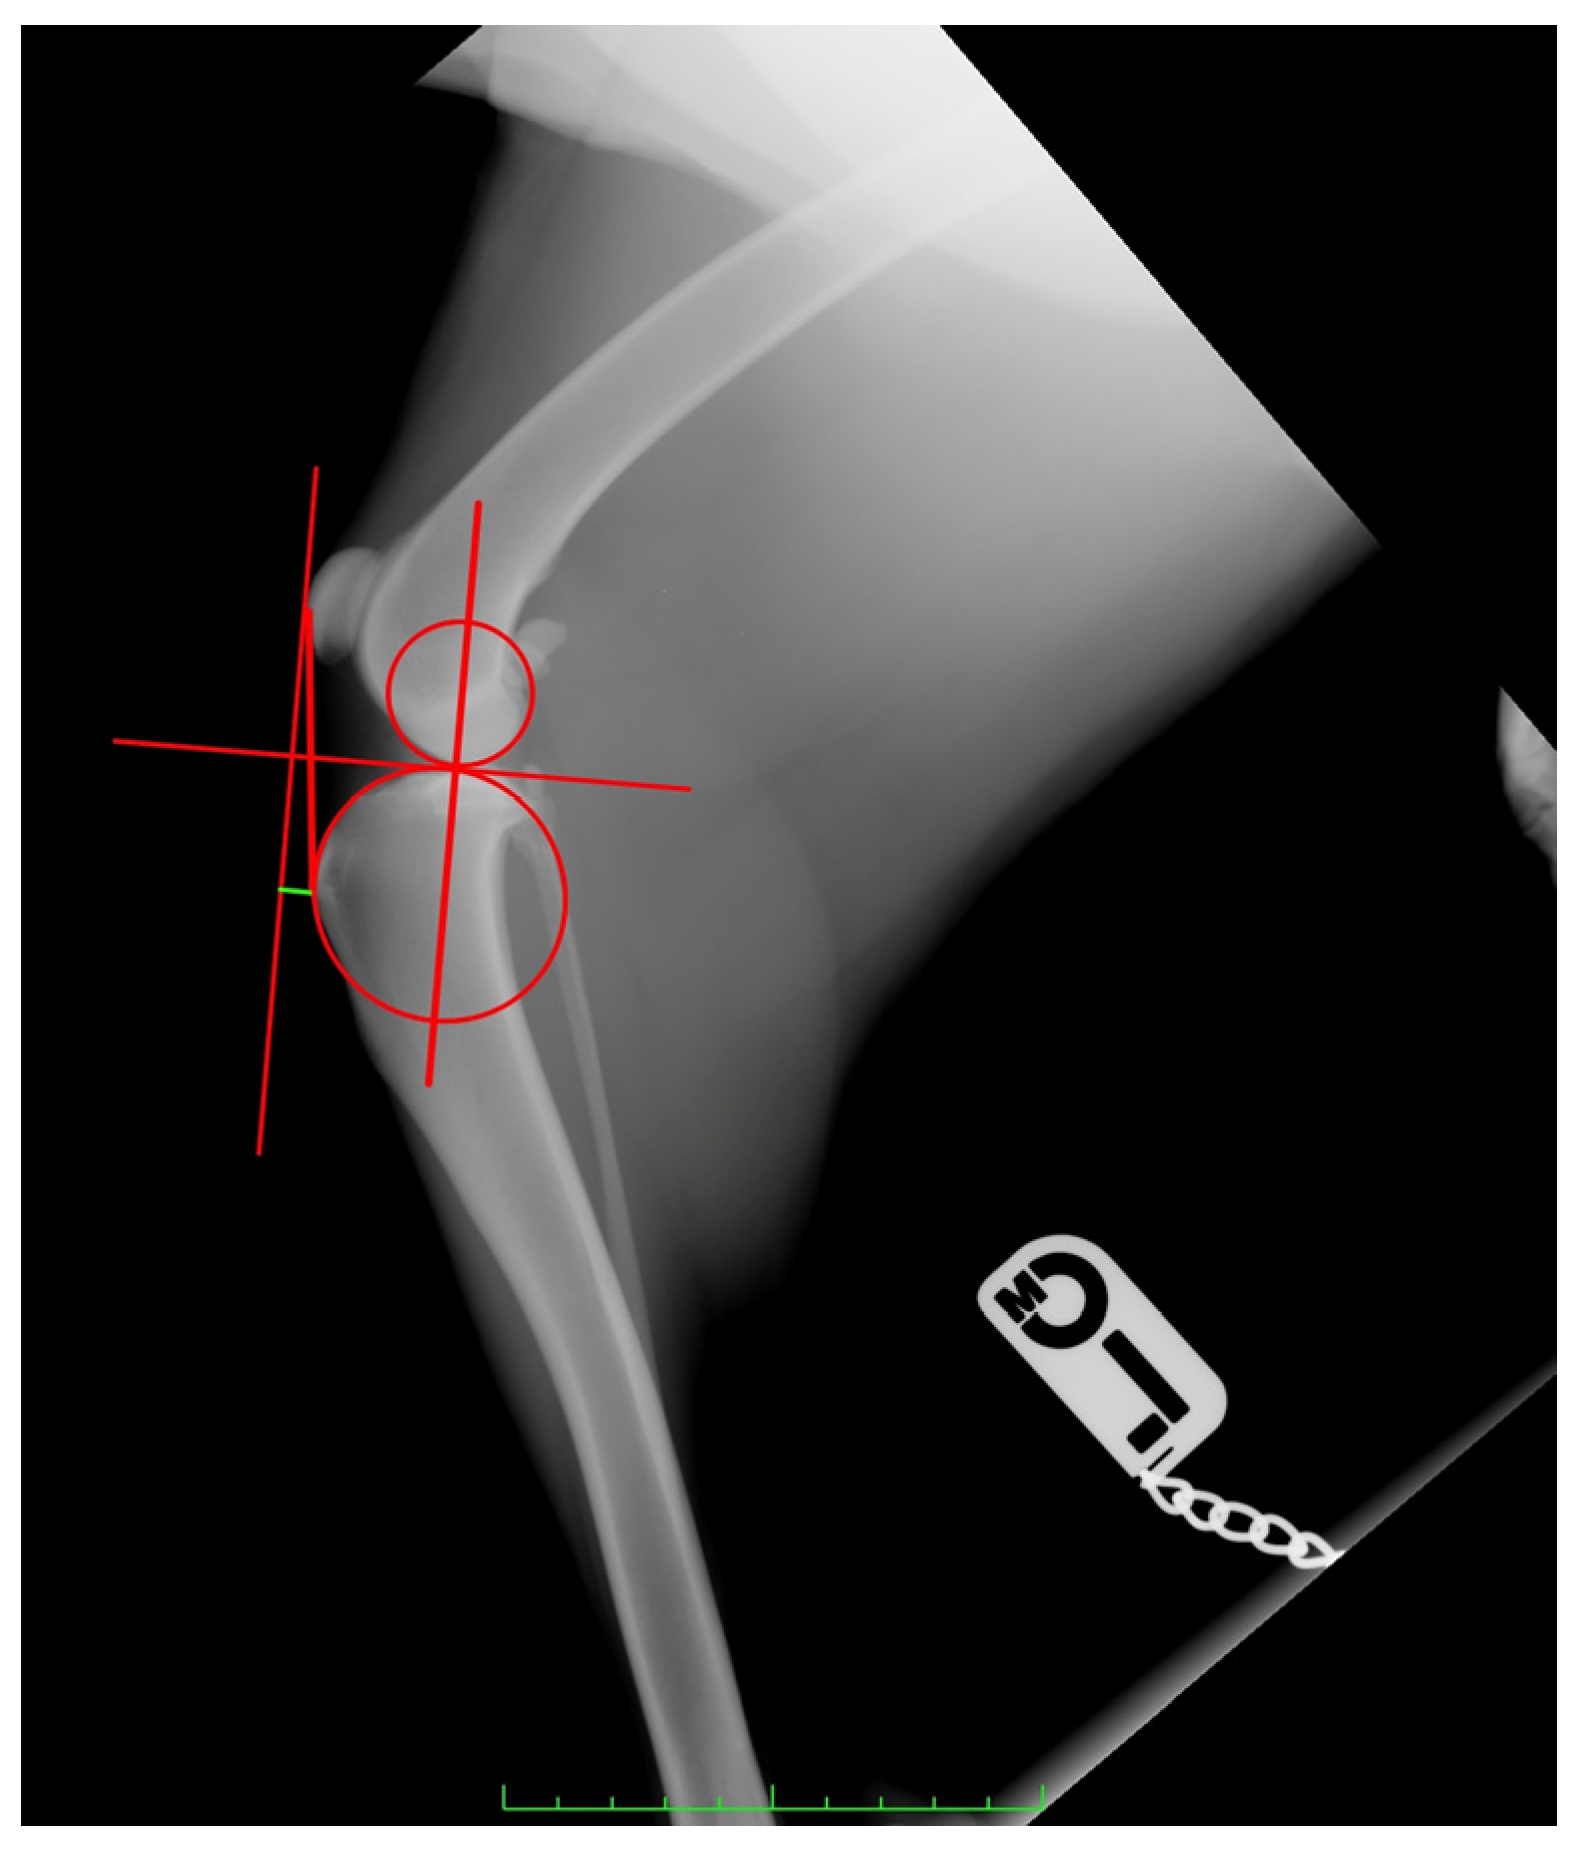

- For CT, first, the observer drew two circles representing the femoral and tibial condyles, marking the center. Next, he connected the two centers with a line and drew a line perpendicular to it, defined as the common tangent. The angle between the common tangent and the line drawn from the caudal margin of the patella to its insertion on the tibial tuberosity corresponded to the PTA. To measure the amount of advancement required, the observer considered the distance between the tibial tuberosity and the line perpendicular to the common tangent starting from the cranial margin of the patella [35] (Figure 1).